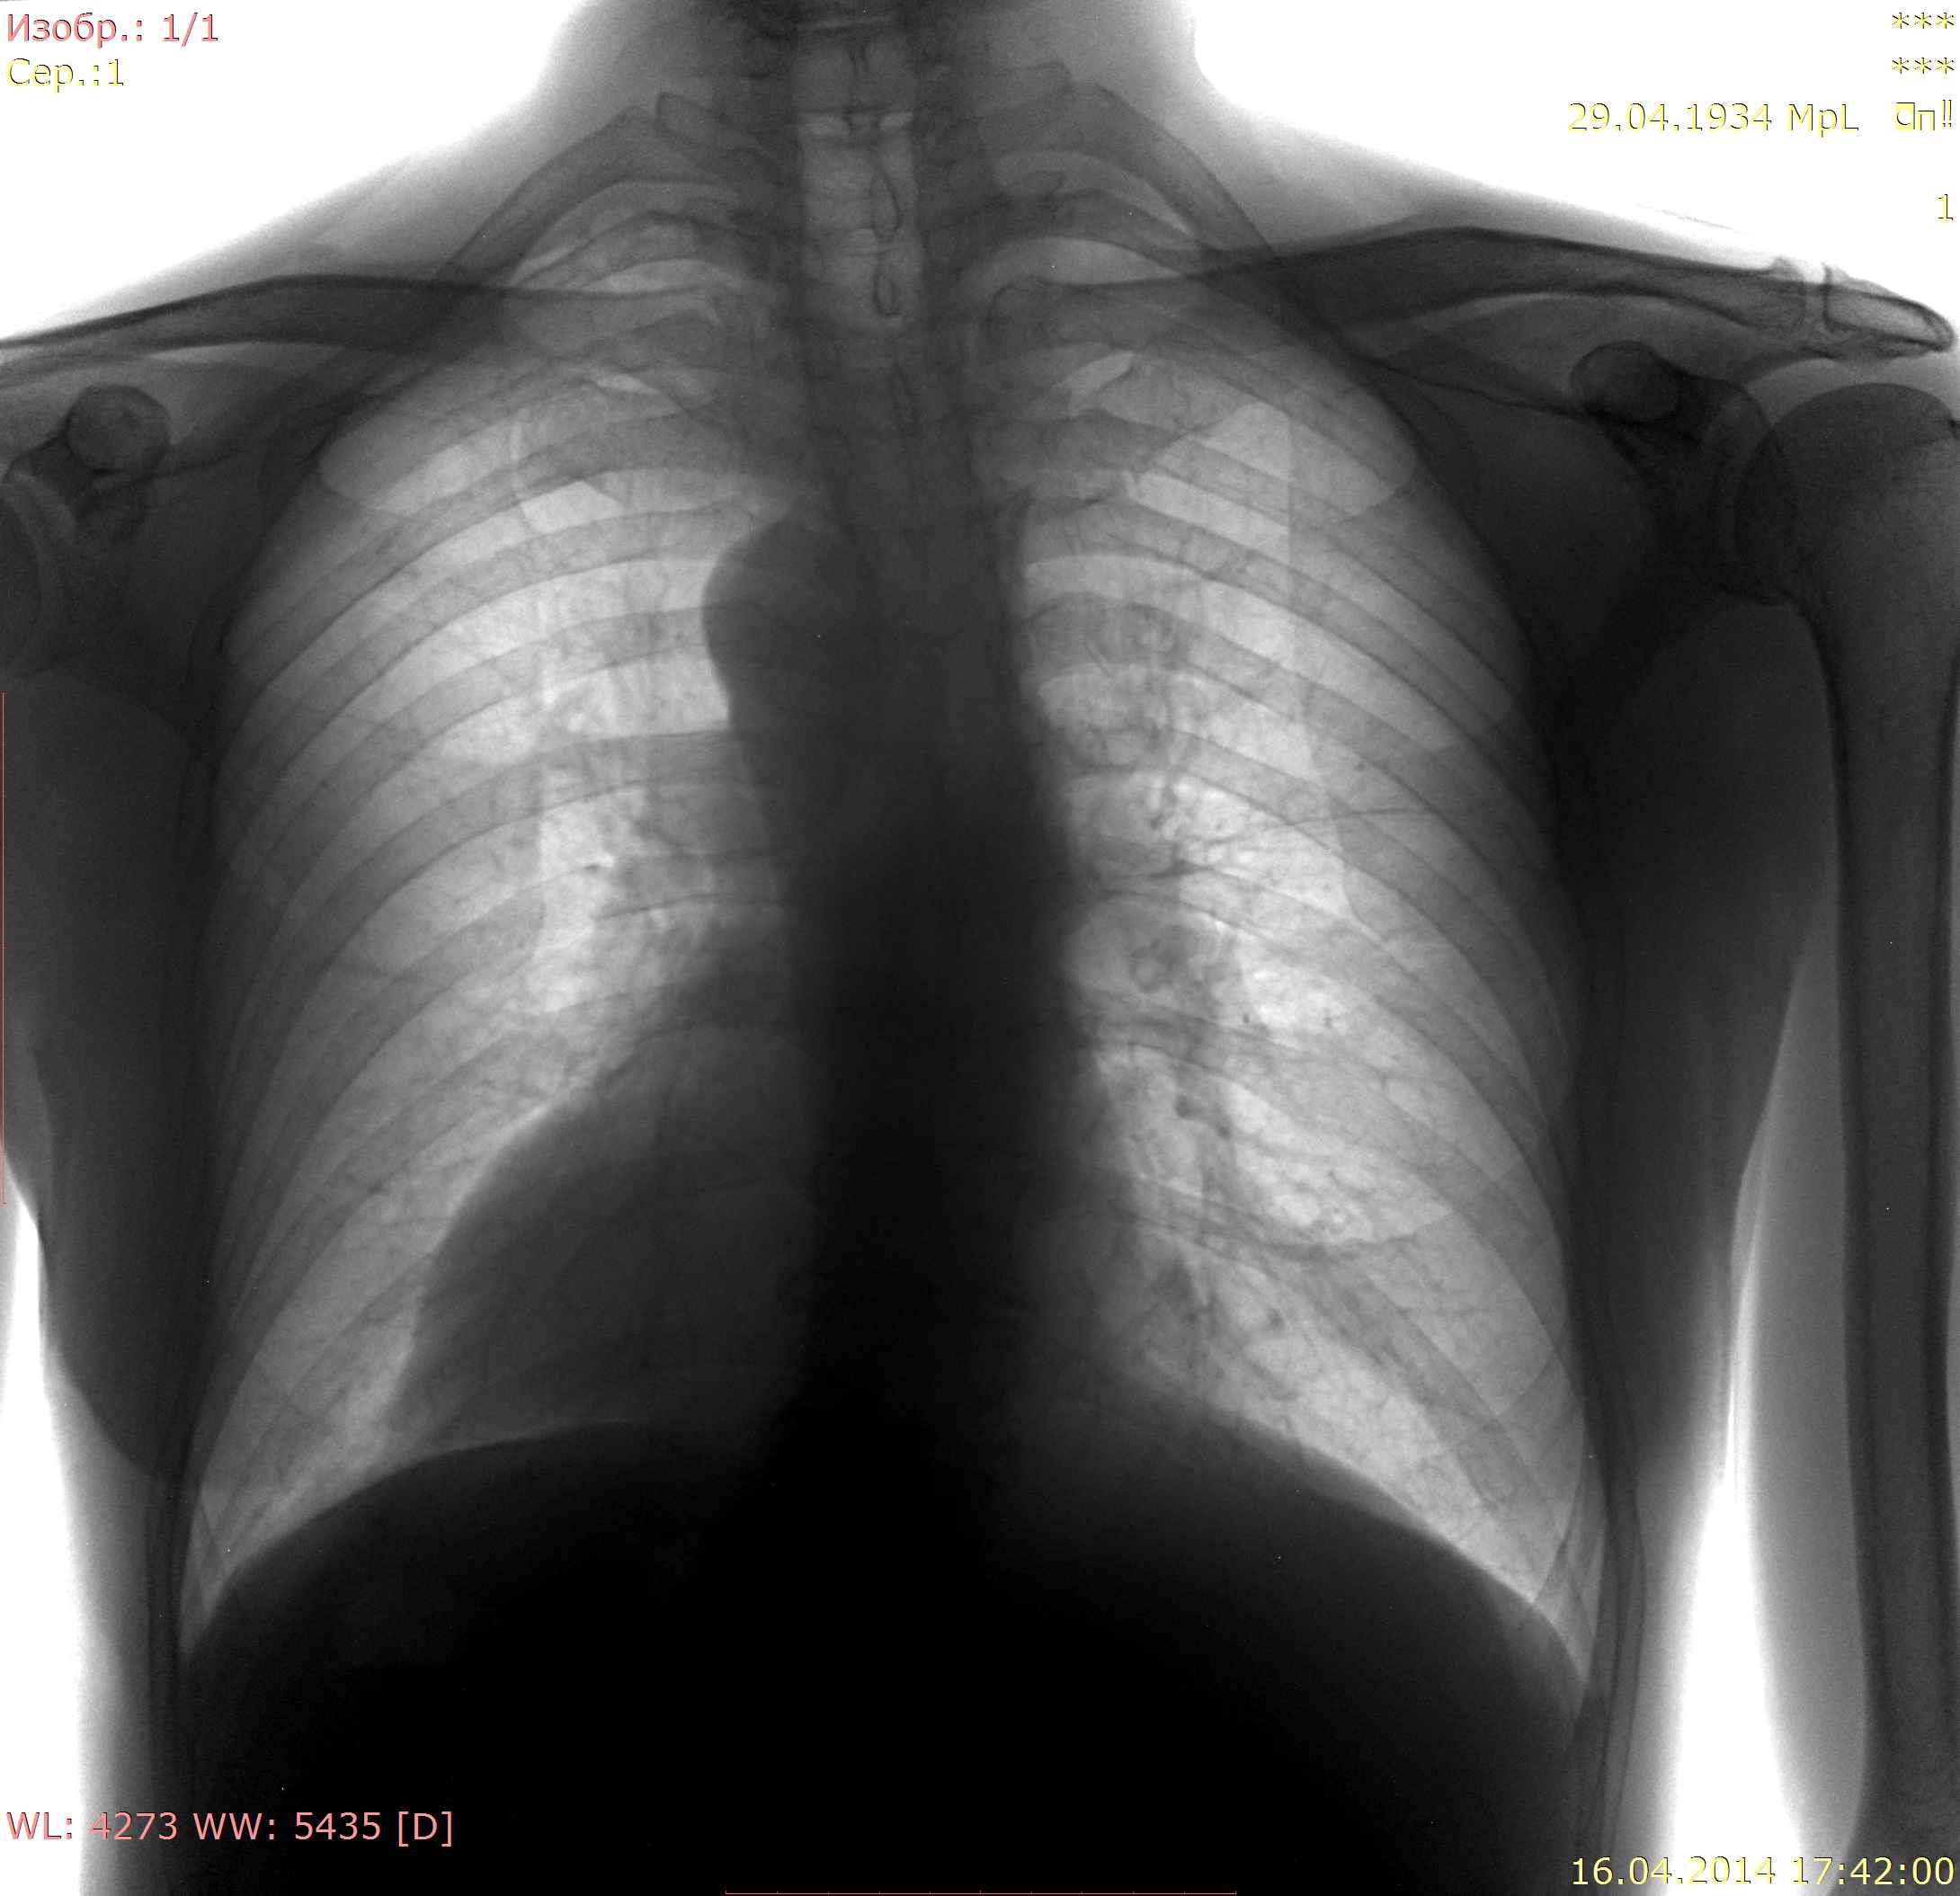

Проф флг, 1938 г.р, не понятна тень на 2 ребре справа, архива нет.

Да, есть тень. Мне кажется, в S3. Подозрительна на Мts (довольно округла, средней интенсивности) Но, учитывая усиление легочного рисунка в сегменте, может оказаться банальной очаговой пневмонией.В моей объективной реальности - рентгенконтроль после противовоспалитеьного лечения.

Да, тень, требующая разбирательства после п\воспалительного лечения